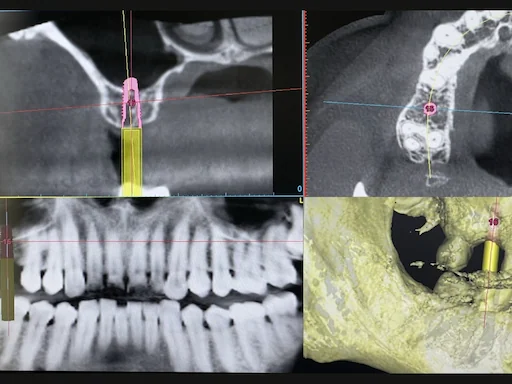

Patientenfall Implantologie: Fehlender Zahn 16 - Implantatplanung

Schritt 2

Anstelle einer Brückenversorgung wurde hier vom Patienten eine implantatgetragene Versorgung gewünscht. Die Anfertigung einer 3D-Aufnahme zeigte, dass die vertikale Knochensituation zwar primär eine Implantatinsertion zuließ, jedoch zusätzlicher Platz in der Kieferhöhle durch einen sogenannten internen Sinuslift geschaffen werden musste.